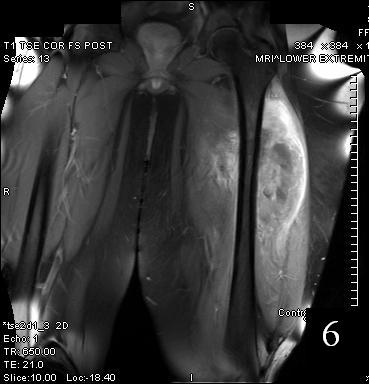

Fig. 5

Fig. 6

Fig. 5-6 Axial (Fig. 5) and coronal (Fig. 6)T1 post contrast MRI shows a heterogenous mass with enhancement post contrast